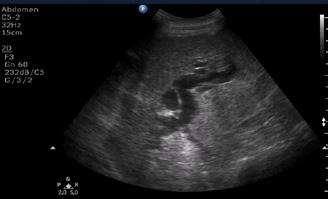

Figura 1. Pacient de 57ani cu simptomatologie acută sugestivă pentru AVC ischemic acut: CT -ul nativ nu a decelat elemente de semiologie sugestive pentru AVC ischemic acut (A), însă secvențele IRM au evidențiat o arie în hipersemnal FLAIR (B) și cu restricție de difuzie (C) localizată occipital paramedian dreapta, sugestivă pentru AVC ischemic acut (Spitalul Clinic de Urgență „Prof. N. Oblu“, Iași)

În contrast, imagistica prin rezonanță magnetică, în special secvențele de difuzie, oferă o sensibilitate superioară pentru detectarea precoce a infarctului ischemic,

fiind capabilă să identifice modificări la nivel celular la doar câteva minute după debutul simptomelor (Figura 1) (Mouridsen et al., 2020), (Nukovic et al., 2023). De asemenea, IRM este capabilă să ofere o evaluare superioară a integrității parenchimului cerebral, a viabilității țesutului și a extinderii leziunii ischemice, facilitând o caracterizare mai detaliată a AVC-ului ischemic (Cortés-Albornoz et al., 2025).